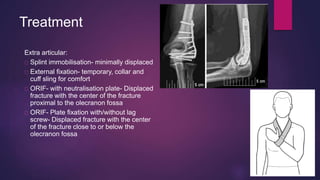

Extra articular:

Splint immobilisation- minimally displaced

External fixation- temporary, collar and

cuff sling for comfort

ORIF- with neutralisation plate- Displaced

fracture with the center of the fracture

proximal to the olecranon fossa

ORIF- Plate fixation with/without lag

screw- Displaced fracture with the center

of the fracture close to or below the

olecranon fossa

Partial articular:

Splint immobilisation

External fixation- for open fractures

ORIF- Screw fixation- treatment of choice

Arthroplasty- Osteoporosis with

unreconstructable articular fragments in

the elderly patient